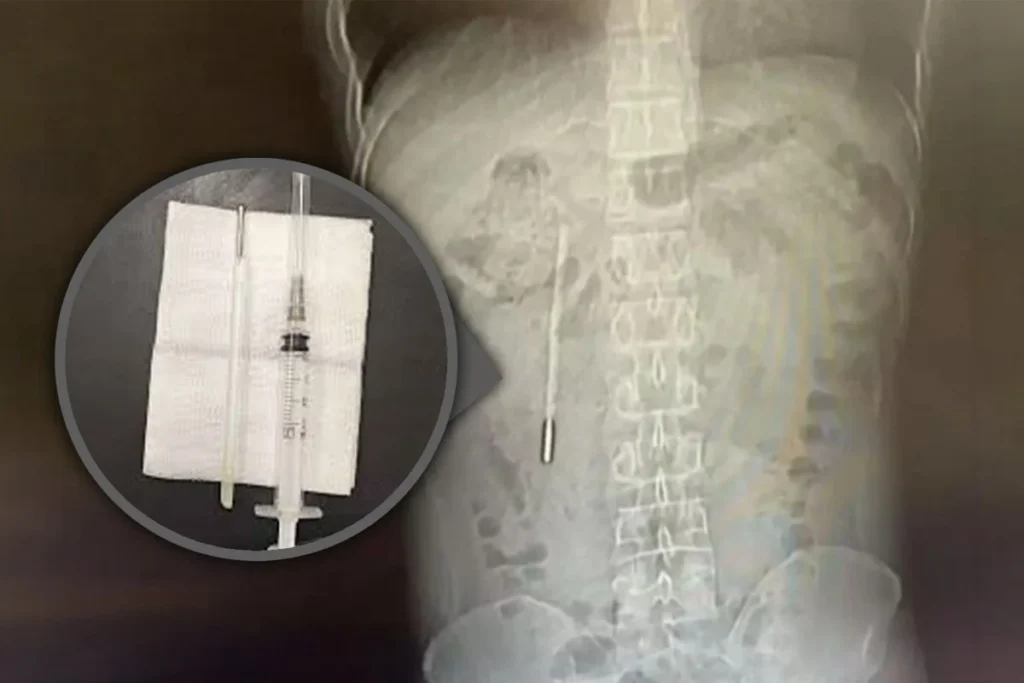

Pacientul s-a prezentat la spital, iar o scanare medicală a arătat prezența unui corp străin în duoden, medicii suspectând că este vorba despre un termometru cu mercur, potrivit South China Morning Post.

Situația era delicată: vârful obiectului apăsa direct pe peretele intestinal, existând risc major de perforație și hemoragie internă severă.

Medicii au reușit să extragă obiectul în doar 20 de minute, însă intervenția a fost una extrem de riscantă.

Termometrul se afla în apropierea canalelor biliare, iar orice mișcare greșită putea provoca leziuni severe ale intestinului.

Dispozitivul a fost scos intact.